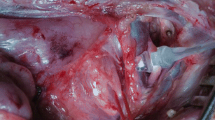

Initially, a pharynx was removed from the warmed storage box, and placed in the lateral position on the laboratory table, where its temperature was measured. Since the lamina superficialis of the cervical fascia, the musculi platysma, sternohyoidei, and sternomastoidei were already removed by the butchers; the dissection focused on the lateral side of the pharynx. Beginning in the now-connected Trigonum caroticum, the superficial connective tissue was removed, and the RLN was located in the groove between the trachea and esophagus. The nerve was then carefully separated from its surrounding tissue. Depending on the highly individual condition of the specimen, the nerve was exposed over approximately ten to thirty centimeters while remaining within the pharyngeal tissue complex. Finally, the nerve was irrigated with Ringer's lactate, and its length and diameter were measured.